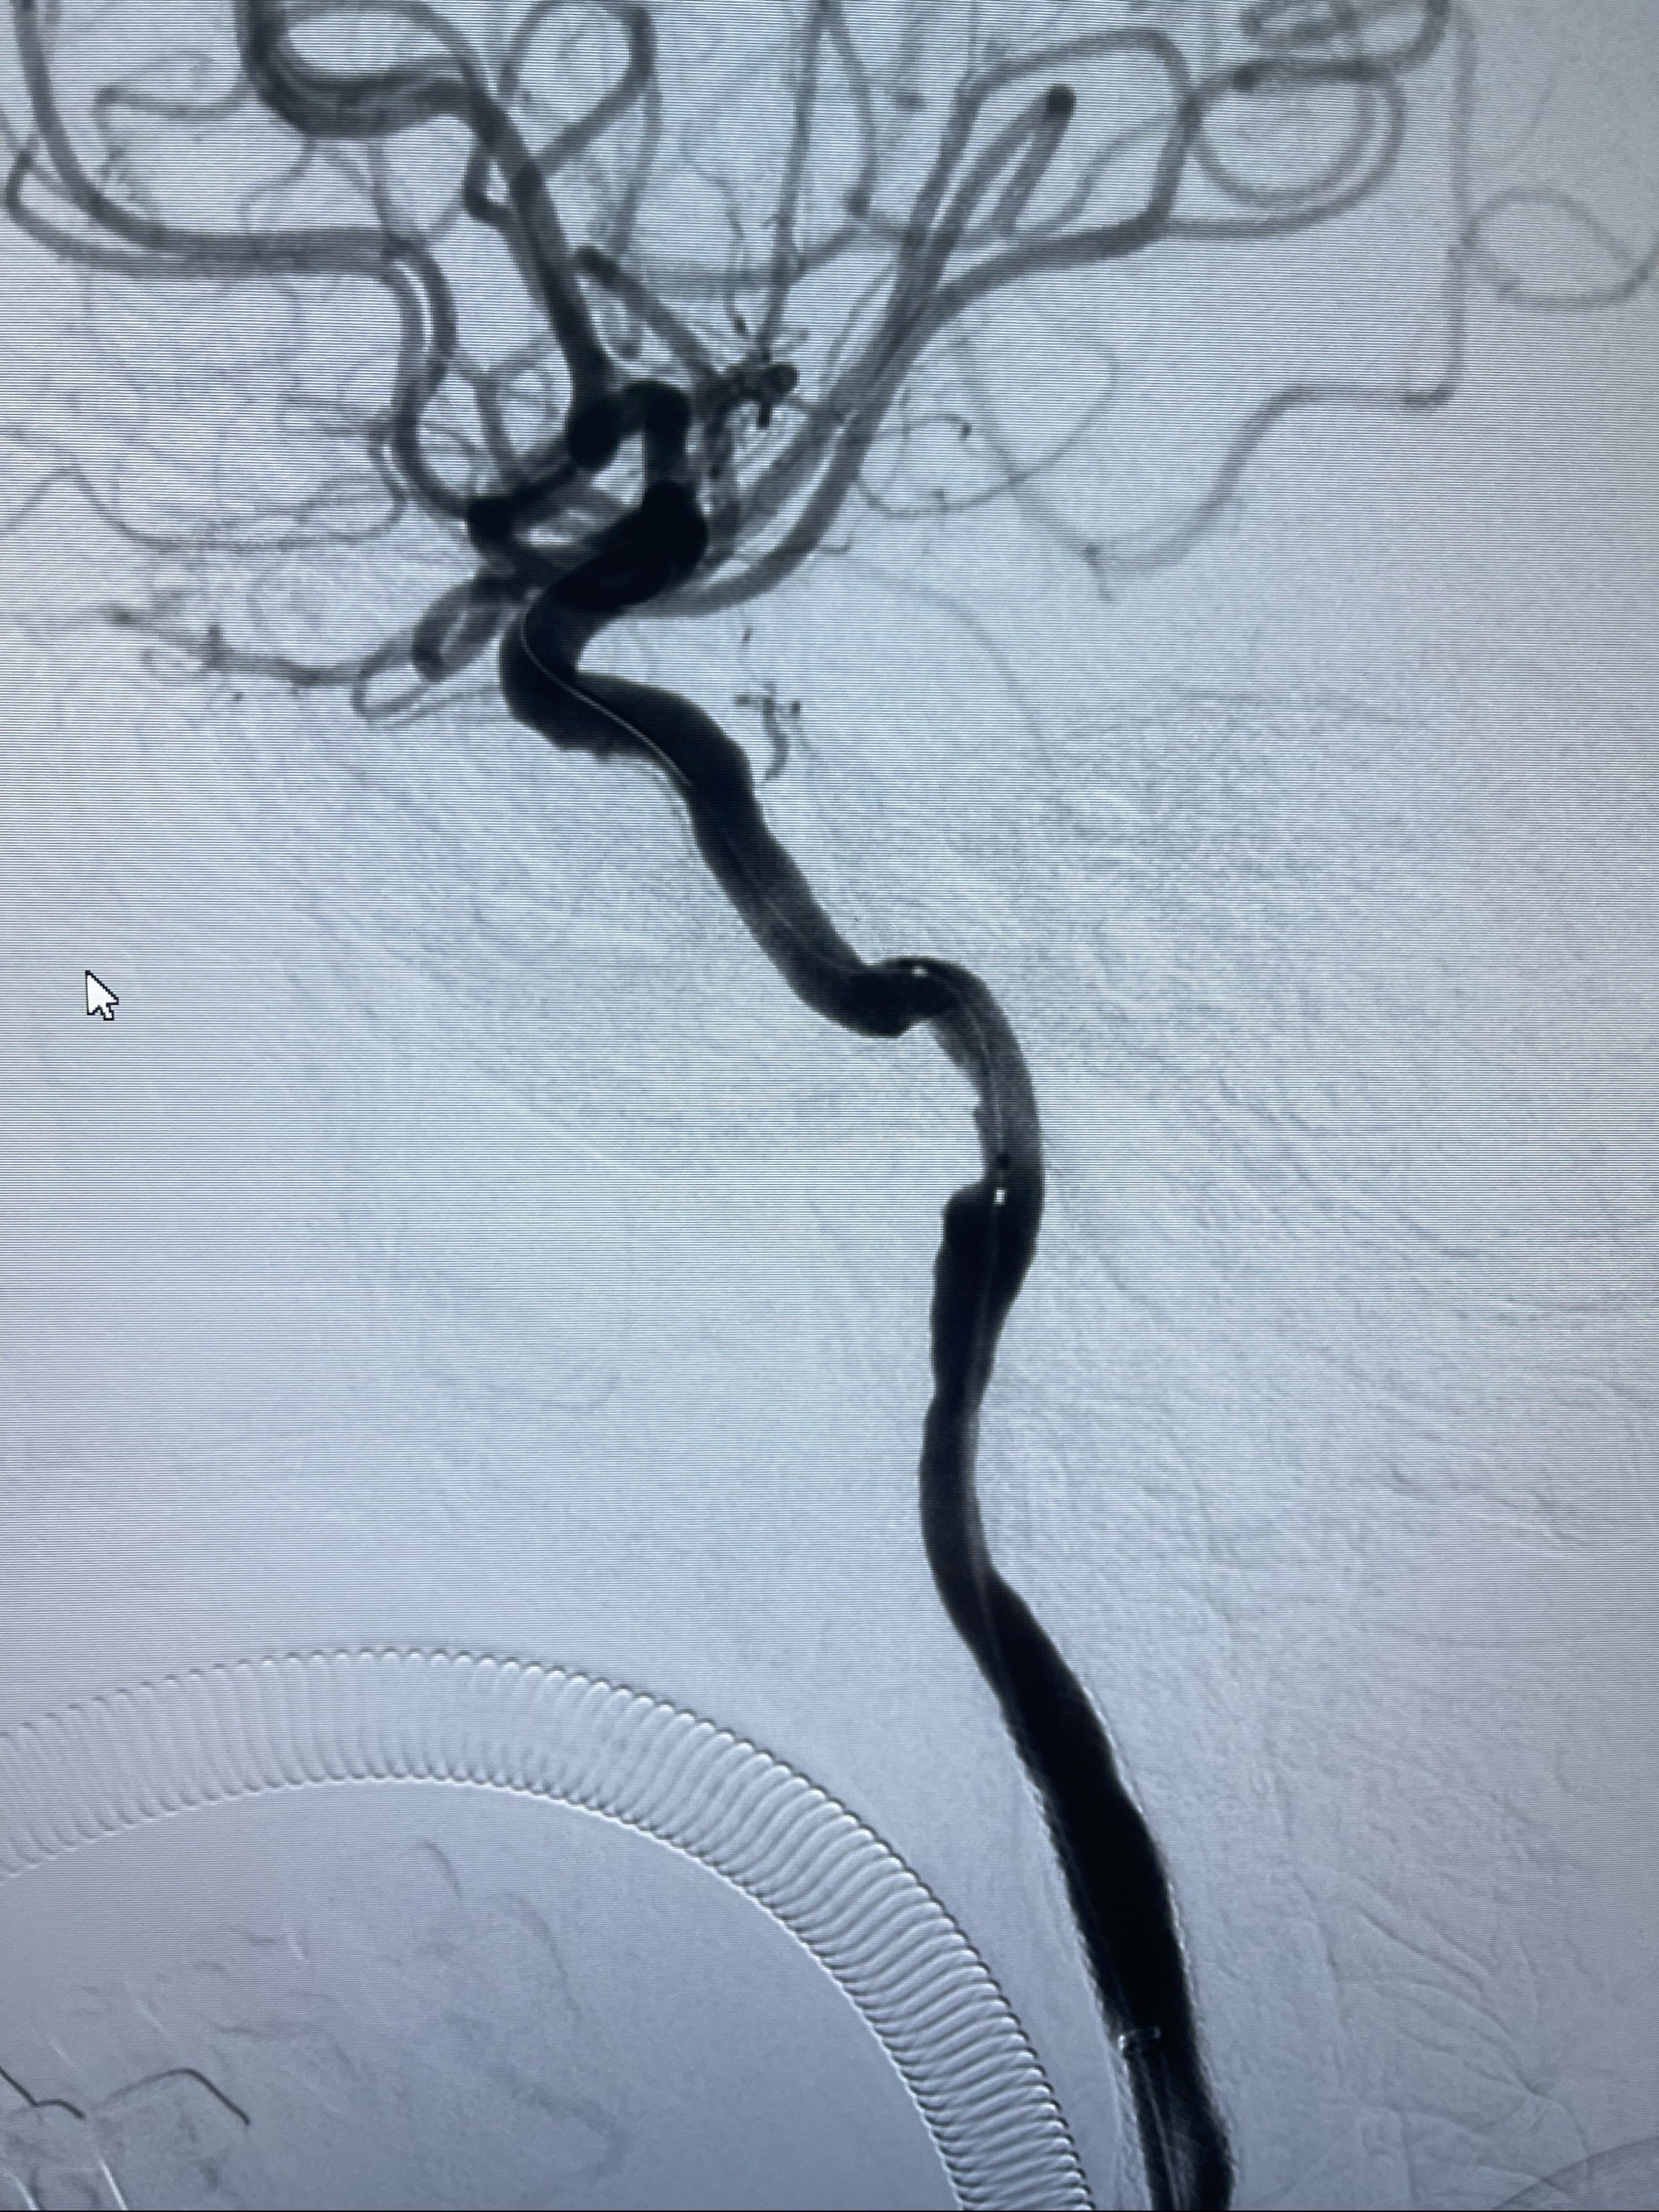

泄除球囊造影显示局部管腔扩张佳

后移球囊至颈段狭窄段,以8-12个大气压扩张,持续30s后泄除球囊

即刻造影显示狭窄扩张佳

重新行“路径图”,支架导管在微导丝引导下超选择性插入至右侧颈内动脉眼段,4.5-50mmLeo支架释放,远心端位于海绵窦段,近心端位于岩骨段狭窄段以近

即刻造影显示支架贴壁佳